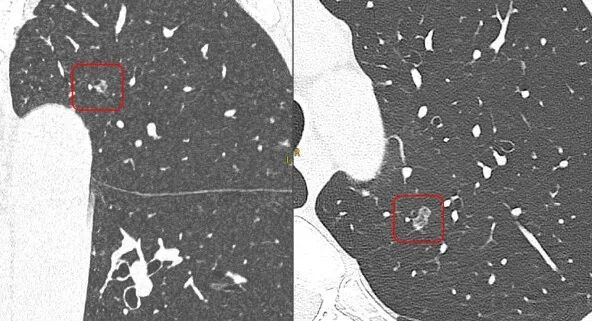

当前,全球放射学专家将目光投向了光子计数CT,这无疑是CT技术的未来灯塔。

这款被视作 “EID CT天花板级产品”的1024层CT,与此前获批的全球首台宽体光子计数CT NeuViz P10形成技术互补。前者以成熟平台实现高端影像普惠,后者以尖端技术定义未来方向,双线布局彰显中国高端医疗装备的战略跨越。

在大范围血管成像领域,NeuViz 1024也表现突出。进行肺部等大范围血管成像时,患者无需长时间屏气,一次快速扫描即可完成。